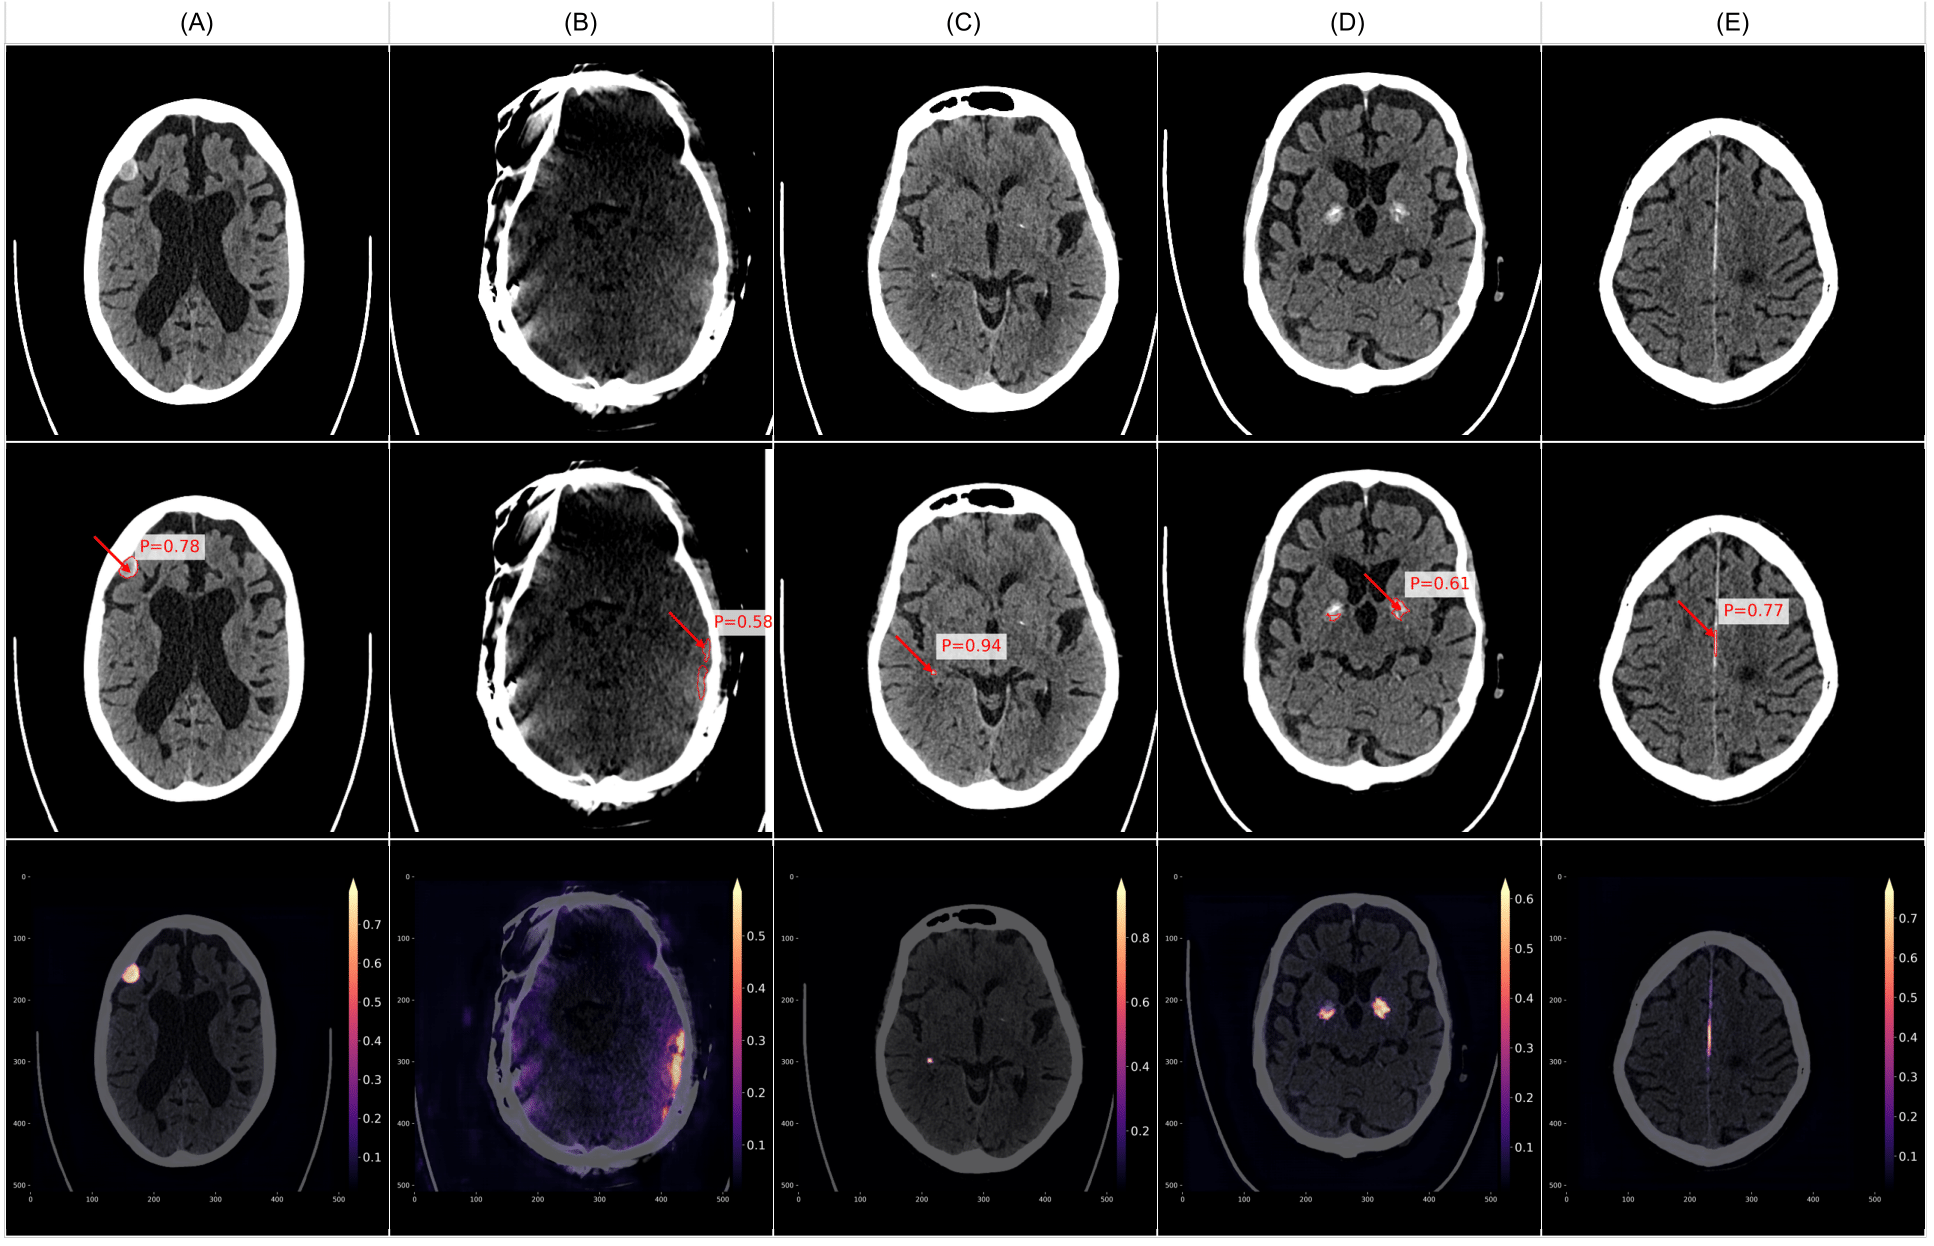

To provide a more intuitive understanding of VIOLA-AI’s performance, we have selected several representative cases for illustration, i.e., True positive case examples (Figure 9), False positive case examples (Figure 10), and False negative case examples (Figure 11).

Figure 10 illustrates examples of false positive cases, where VIOLA-AI incorrectly identified ICH in CT scans that did not contain any bleeds. These misclassifications often arise because some bleed-like features closely resemble non-hemorrhagic structures. Contributing factors include imaging artifacts (e.g., B: motion artifacts) and the model’s heightened sensitivity to certain high-density regions, such as various calcifications. Examples include A: a partly calcified meningioma, C: choroid plexus calcifications, D: basal ganglia calcifications, and E: falx and dura calcifications. Analyzing these false positives is crucial for refining the model to better distinguish between true hemorrhages and similar-looking non-bleed findings, thereby improving overall accuracy.